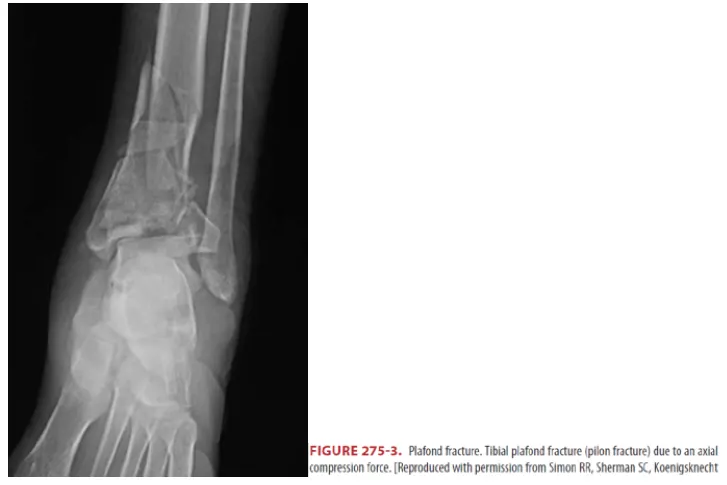

E2. Pilon (Plafond) fractures

•

족부의 axial force에 의해 talus를 통해 tibia의 관절면으로 충격이 진행하여 원위경골이 grinding 되거나 crusing될 수 있다.

x-ray는 한쪽 view만을 보이기 때문에 CT를 반드시 시행해야 한다.

구획증후군이나 척추 몸통 (특히 요추 1번)의 골절을 동반할 수 있음

치료 목표 : 골절편을 맞추고 관절면을 맞추는 것